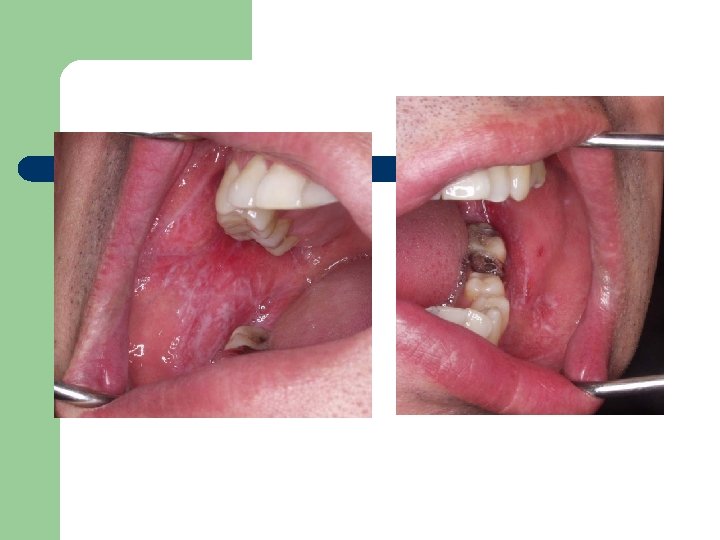

Case Report 1 27 Y/F 초진 : Lt. lower buccal area 1개월 전부터 ulceration

Case Report 1 27 Y/F 초진 : Lt. lower buccal area 1개월 전부터 ulceration EX. Bx. 1주일 후 : f/u

Case Report 2 l l 37/M 초진: 4개월 전부터 입안이 쓰리고 아픔 Both lower

Case Report 2 l l 37/M 초진: 4개월 전부터 입안이 쓰리고 아픔 Both lower buccal mucosa ulceration white patch Rx) Oradex. 10 A + saline 100 cc • 1주일 후: 증상호전